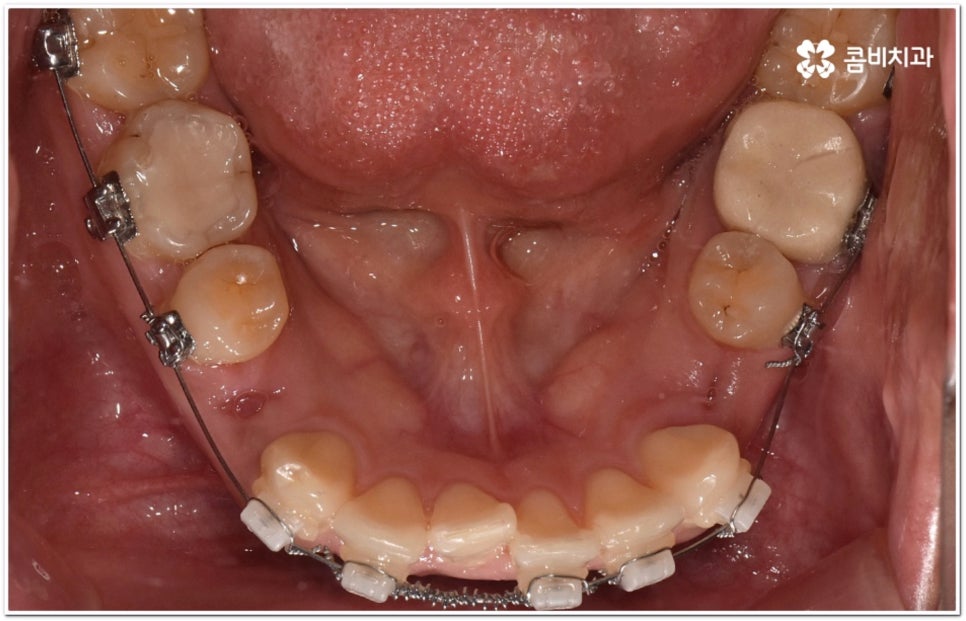

환자마다 치열, 교합, 치아가 튀어나온 각도, 잇몸이 드러나는 정도, 상악과 하악의 구조 및 관계 등 턱관절 관련 부분 상황이 모두 다르기 때문에 3D CT 같은 정밀 검진 기계를 통해 이를 꼼꼼하게 살펴보고 각각에 맞는 계획을 세밀하게 세워 교정 치료를 진행해 줄 필요가 있어요. 이때 환자분들의 상황에 따라 양악수술과 같은 외과적인 방법을 병행해야 하는 케이스도 있을 수 있기 때문에 돌출입을 가지고 계신 분들 중에서 수술에 부담을 느끼고 지레 치료를 포기하신 분들도 있을 수 있는데 정도가 많이 심각하지 않고 구조적인 원인이 크지 않다면 대부분의 케이스는 치아교정 만으로도 충분히 개선이 가능하니 먼저 돌출입교정치과 에 들러서 정밀 검사를 진행한 후 치료 방향에 대해 의료진과 논의해 보시면 좋을 거예요.

말씀드렸던 것처럼 돌출입의 원인이 치아 만의 문제, 즉 각도가 살짝 앞으로 뻐드러진 데 있고 상태가 그다지 심한 것 같지 않다면 보다 빠르고 간편한 수복이 가능할 수 있어요. 튀어나온 부분을 집어넣기 위해서는 발치가 필수적이지 않을까 생각하실 수 있는데 후방으로 이동시켜 줄 공간이 충분하다면 치간 삭제, 악궁 확장, 어금니 후방 이동 등 다른 방법을 이용하여 비발치 치료 과정을 진행할 수 있으므로 너무 걱정하지 않으셔도 될 거예요. 오히려 환자분들의 다양한 상황을 고려하지 않고 무리하게 발치 교정을 진행하게 되면 옥니나 합죽이와 같은 부작용이 일어날 수도 있기 때문에 원인을 정확하게 파악하고 적절한 치료를 할 수 있도록 임상 경험이 풍부하고 뛰어난 노하우를 가지고 있는 숙련된 의료진에게 교정 치료를 맡기시는 것이 굉장히 중요하다고 할 수 있습니다.